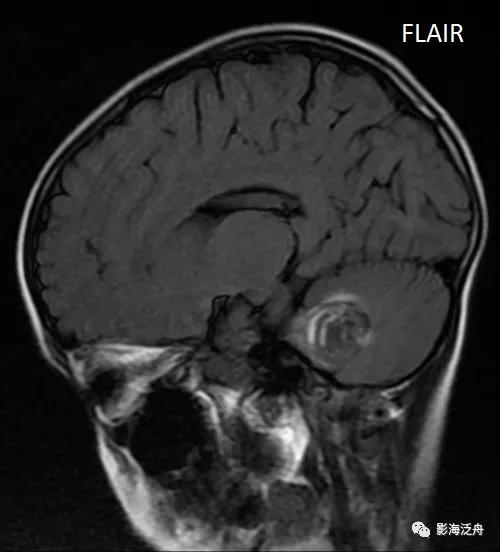

比如本例患者就没有及时进一步检查,只是保守治疗后常规复查,直到一年以后才做了SWI,如下图。

SWI可见左侧大脑半球多发低信号结节(红箭),病灶多位于皮髓质交界区,直径较为一致,结合患者年龄、病史,不难诊断这是一例多发海绵状血管瘤。